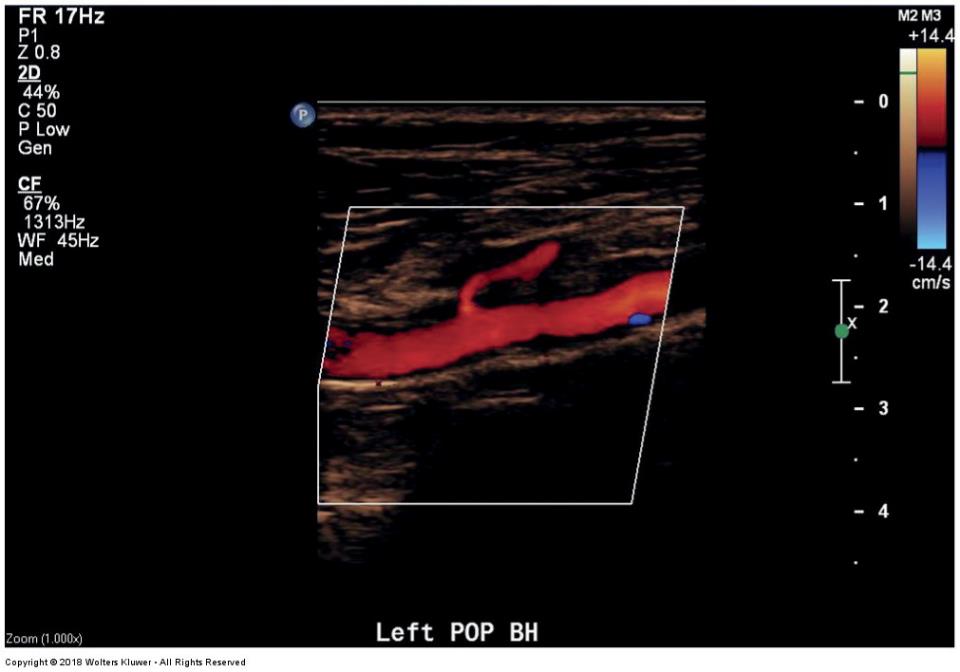

ultrasound image of the popliteal artery with the gastrocnemius artery